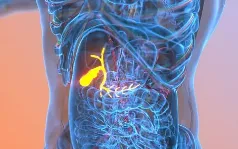

췌장암 초기증상 Best 5, 이것만 기억하세요!

췌장암은 초기에 증상이 없어 발견하기 어려운 암으로 악명이 높습니다. 대부분의 사람들은 췌장이 어디에 위치해 있는지 잘 모르고, 병이 어느 정도 진행된 후에야 통증이 나타나기 때문에 췌